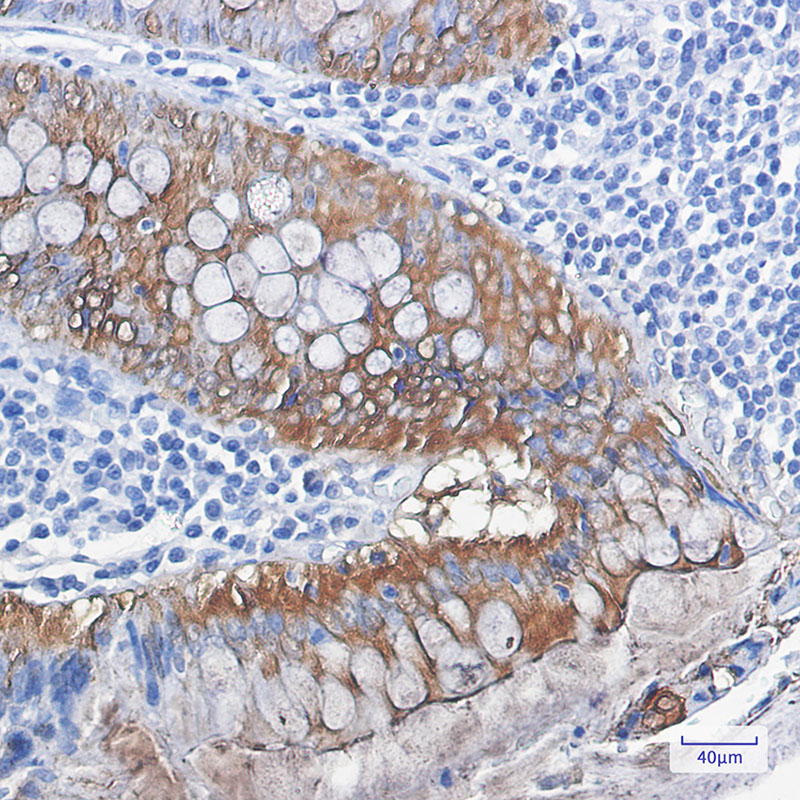

IHC 1/50-1/100 Human,Mouse,Rat

Galectin-3. a member of the β-galactoside-binding lectin family, is a multifunctional protein implicated in cell proliferation, apoptosis, inflammation, and cancer metastasis. Its unique structure, consisting of a carbohydrate-recognition domain (CRD) and an N-terminal proline-rich domain, enables interactions with glycoproteins and glycolipids, modulating intracellular signaling and extracellular matrix organization. Dysregulation of Galectin-3 is associated with fibrosis, cardiovascular diseases, and tumor progression, making it a therapeutic and diagnostic target.